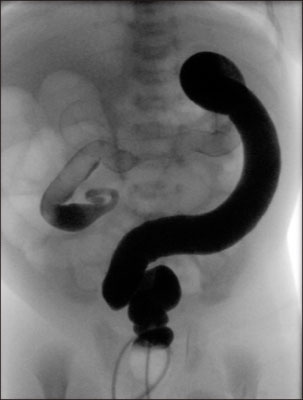

Fig. 2

Total colonic aganglionosis in a 3-day-old boy. Question-mark shape of the colon is noted with cecum and ascending colon. The rectum and descending colon has normal caliber (case 15).

Fig. 2 Total colonic aganglionosis in a 3-day-old boy. Question-mark shape of the colon is noted with cecum and ascending colon. The rectum and descending colon has normal caliber (case 15).